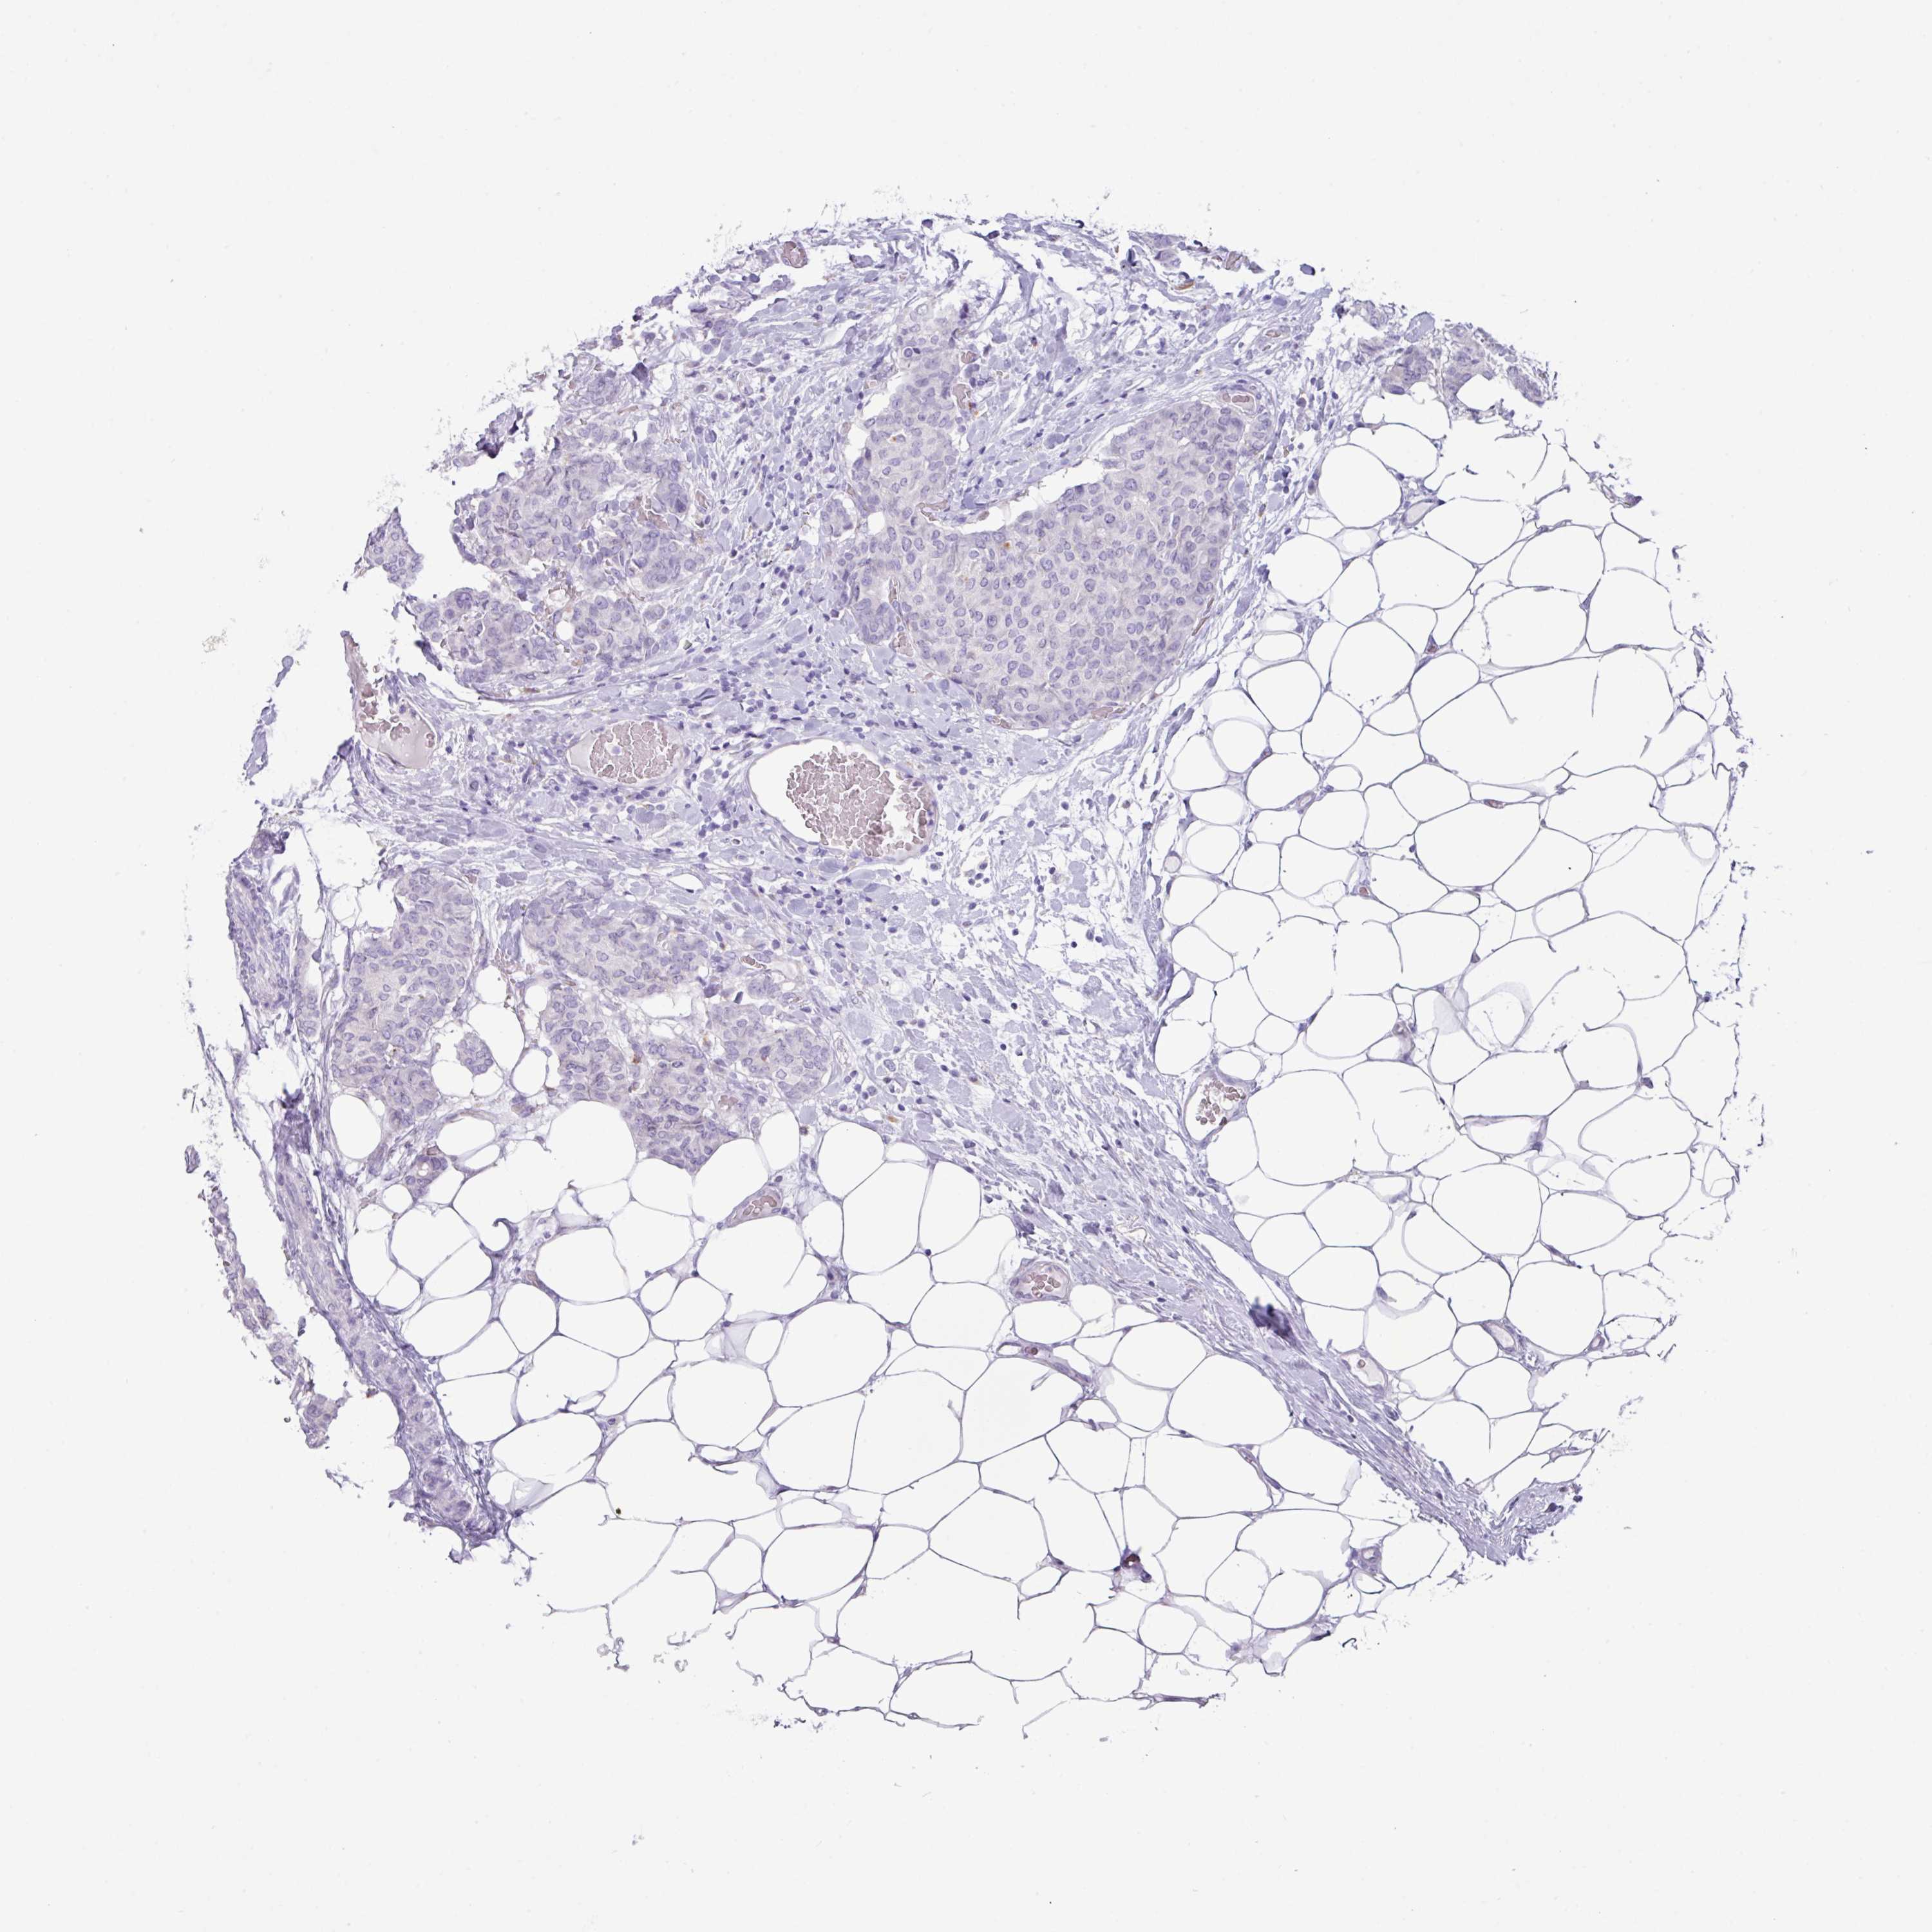

CANCER BREAST CANCER Show tissue menu

Breast cancer

Human cancer